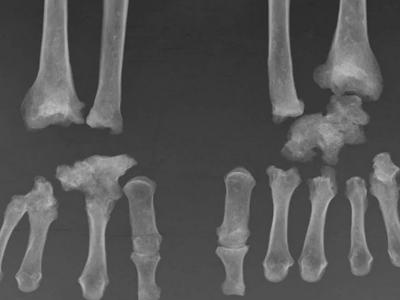

या सांगाड्याची जेव्हा अधुनिक पध्दतीने चाचणी केली जाते. तेव्हा खास करुन स्थूलता आणि डायबिटिस या आजारांनी ग्रस्त असल्याचे समजते.

या सांगाड्यांच्या तपासणीमुळे आधीच्या काळातल्या लोकांना होणारे आजार समजायला मदत होत आहे.

यात कारखान्याजवळ केलेल्या उत्खननात जे सांगाडे मिळाले. त्यावर हिरव्या रंगाचे डाग होते. तज्ञांच्या म्हणण्यानुसार हे डाग केमिकल्सचे असावेत. या खजिन्यातून लंडनच्या इतिहासाच्या अनेक गोष्टी उलगडतील.